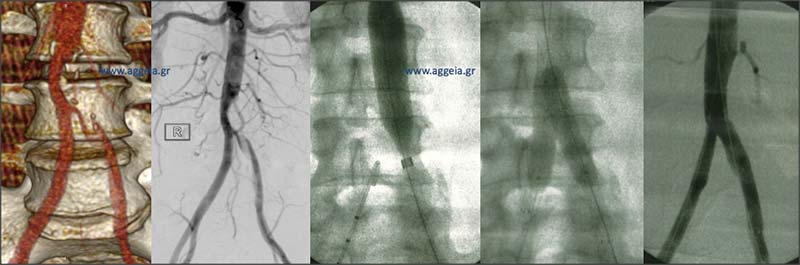

Αγγειοπλαστική λαγόνιων αρτηριών - kissing stents

Απόφραξη ΔΕ λαγονίου αρτηρίας και στένωση αριστερής - Αγγειοπλαστική με kissing stents